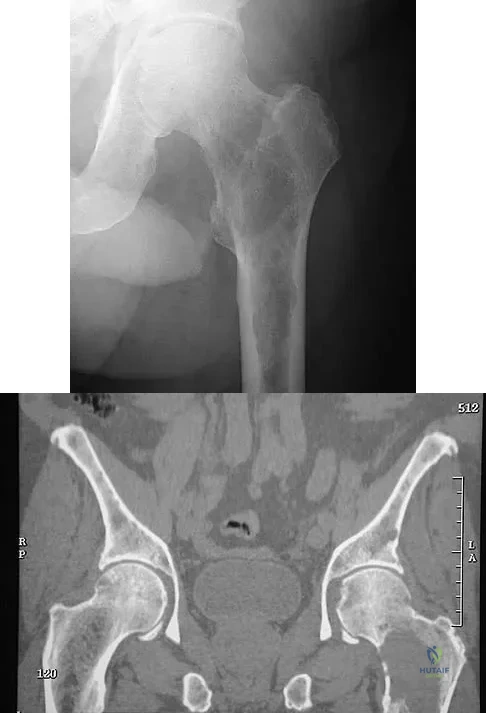

Figures 29a and 29b show the AP radiograph and CT scan of a 70-year-old man who has left thigh pain. Serum protein electrophoresis shows a monoclonal gammopathy. Additional radiographs of the femur show other lesions. Management should consist of

The underlying diagnosis is multiple myeloma. Because the patient has a large lucent lesion in the peritrochanteric region of the left proximal femur, the risk of pathologic fracture is high. Consideration should be given to prophylactic internal fixation with a locked intramedullary rod. The lesion does not appear to be a sarcoma requiring wide resection and endoprosthetic reconstruction. Neither chemotherapy nor radiation therapy alone is likely to result in long-term stabilization of the proximal femur. Postoperative treatment with bisphosphonates and radiation therapy is indicated to decrease the risk of future pathologic fractures. The patient should also be referred to a medical oncologist for medical management. Menendez LR (ed): Orthopaedic Knowledge Update: Musculoskeletal Tumors. Rosemont, IL, American Academy of Orthopaedic Surgeons, 2002, p 364.